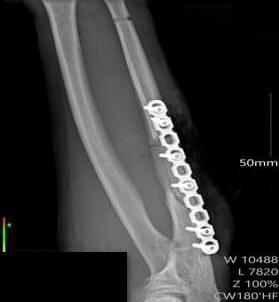

Спустя три недели медики сделали открытую репозицию (процедуру, направленную на сопоставление фрагментов кости после перелома), и погружной остеосинтез локтевой кости пластиной и винтами – фиксирующие элементы установили в область перелома.

Анатомическая целостность локтевой кости была восстановлена, а обширный дефект мягких тканей рук устранен.

Пациент выписан из стационара в удовлетворительном состоянии.